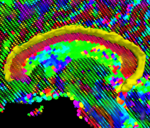

ZoomedResultWithModel.png

Geodesic Active Contours for Fiber Tractography and Fiber Bundle Segmentation

In this work, we provide an energy minimization framework which allows one to find fiber tracts and volumetric fiber bundles in brain diffusion-weighted MRI (DW-MRI).

New: J. Melonakos, E. Pichon, S. Angenet, and A. Tannenbaum. Finsler Active Contours. IEEE Transactions on Pattern Analysis and Machine Intelligence, 2007 (in press).